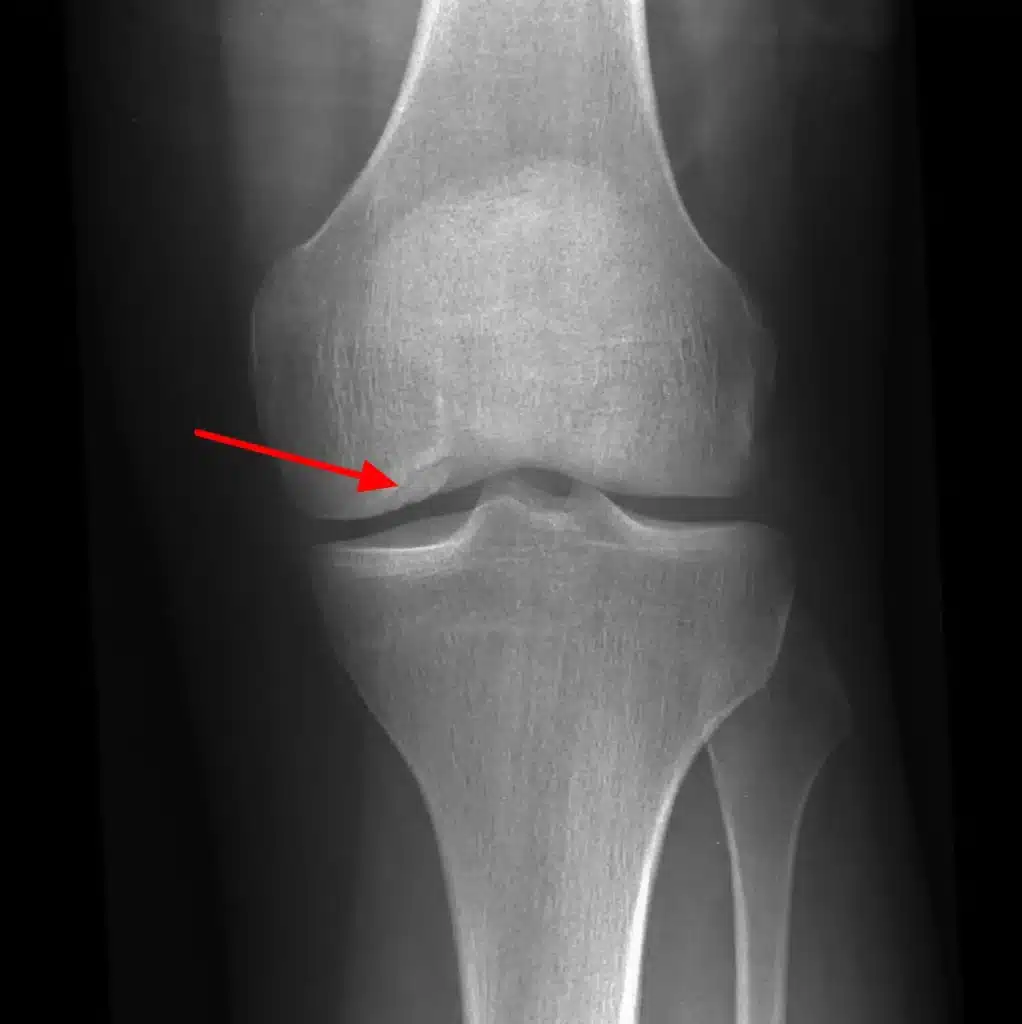

استئوکندریت چیست

اگر دردی مبهم و مزمن در مفاصل خود حس میکنید، ممکن است دچار یکی از اختلالات استخوان و غضروف شده باشید. استئوکندریت یکی از مهمترین آنهاست.جهت کسب مشاوره رایگان با شماره 09106063586 تماس حاصل فرمایید. استئوکندریت چیست؟ انواع، علائم و درمان این بیماری غضروفی ✔ انواع استئوکندریت استئوکندریت می تواند در مفاصل مختلف بدن رخ […]